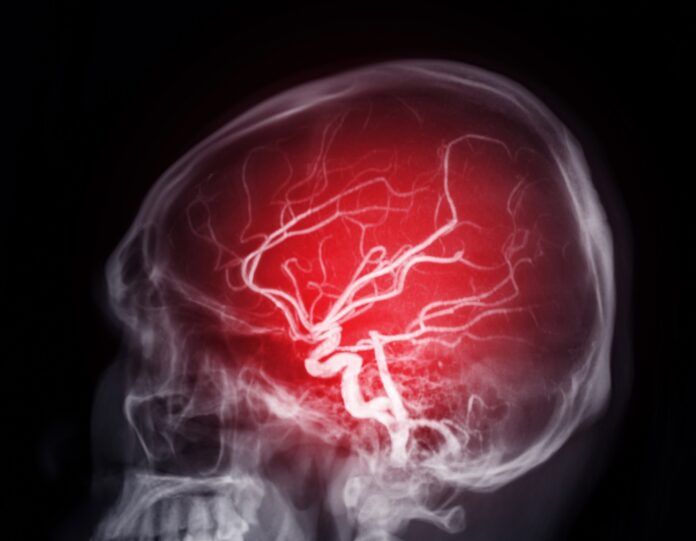

Le neurologue David Devos, médecin et professeur en pharmacologie médicale à l’université de Lille, spécialiste de la maladie de Parkinson, explique la spécificité de ce contaminant. Les solvants, dont l’hexane, ont « une affinité » avec les gras. Le cerveau est riche en gras. En pénétrant l’organisme, par exemple par inhalation ou par le biais de l’alimentation, le solvant va affecter directement un organe riche en graisses comme le cerveau.

Le caractère neurotoxique de l’hexane est connu depuis plusieurs dizaines d’années. Dès les années 1970, aux Etats-Unis comme en Europe, les scientifiques avaient mis en lumière la responsabilité de l’hexane dans la multiplication de maladies de Parkinson chez des ouvriers produisant ce solvant. Aujourd’hui, alors que les maladies neurodégénératives explosent dans le monde, on commence à réaliser l’incroyable potentiel de destruction des neurotoxiques. En mars 2025, la revue scientifique The Lancet Neurology a publié des chiffres sidérants. En l’espace d’une trentaine d’années, l’ensemble des pathologies neurologiques (Alzheimer, AVC, méningites, Parkinson…) ont bondi de 50%. En 2021, 3,4 milliards de personnes, c’est-à-dire 43% de la population mondiale, ont été touchées par une maladie neurologique.

Les affections neurologiques (1) qui comprennent un large éventail de pathologies sont devenues la principale cause de morbidité, avant les maladies cardiovasculaires. Dès lors, on ne peut que s’affliger du manque de fermeté des pouvoirs publics dans le dossier de l’hexane.

(1) Selon l’OMS, les dix principales affections neurologiques sont l’accident vasculaire cérébral, l’encéphalopathie néonatale (lésion cérébrale), la migraine, la démence, la neuropathie diabétique (lésion nerveuse), la méningite, l’épilepsie, les complications neurologiques liées à la prématurité, les troubles du spectre autistique et les cancers du système nerveux.